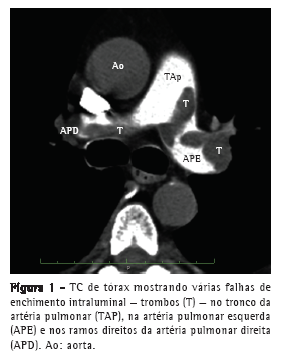

Um homem de 63 anos procurou o Hospital Pablo Tobon Uribe, em Medellín, na Colômbia, com queixa de dispneia nas duas semanas anteriores. O exame físico revelou taquicardia, taquipneia, hipertensão leve, distensão venosa jugular, distensão abdominal e edema nos membros inferiores. Entretanto, os achados cardíacos e pulmonares foram normais. O eletrocardiograma revelou apenas taquicardia sinusal. O paciente apresentou troponina I cardíaca = 0,2 ng/mL (normal: < 0,04 ng/mL) e pró-peptídeo natriurético cerebral N-terminal = 3.590 pg/mL (normal: < 125 pg/mL). A TC helicoidal de tórax realizada posteriormente confirmou a presença de EP ao revelar falhas de enchimento no tronco da artéria pulmonar e em seus ramos principais (Figura 1). A ultrassonografia venosa revelou trombose venosa profunda iliofemoral esquerda. O paciente passou então a receber heparina intravenosa.